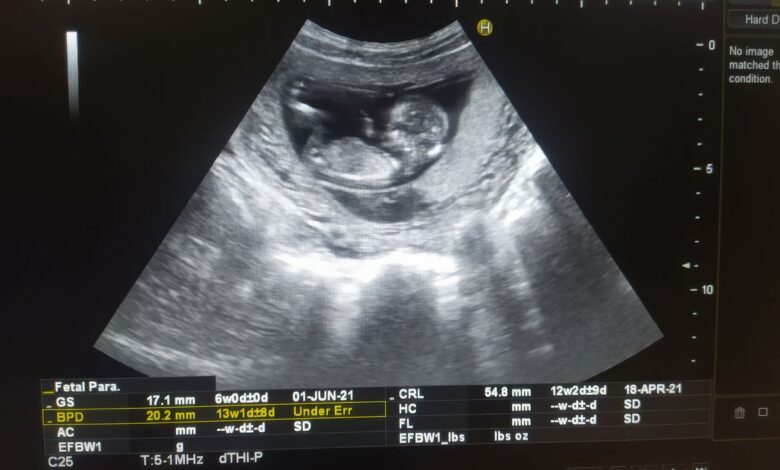

Una de las mayores preocupaciones en torno a estos químicos es la exposición prenatal y durante la infancia. Los PFAS llegan al feto a través de la madre, que los incorpora por agua, alimentos o productos contaminados. Estos compuestos atraviesan la placenta sin dificultad y se acumulan en el organismo en desarrollo, uniéndose a proteínas de la sangre y a órganos clave. Estudios previos han asociado la exposición prenatal con bajo peso al nacer y mayor riesgo de parto prematuro.